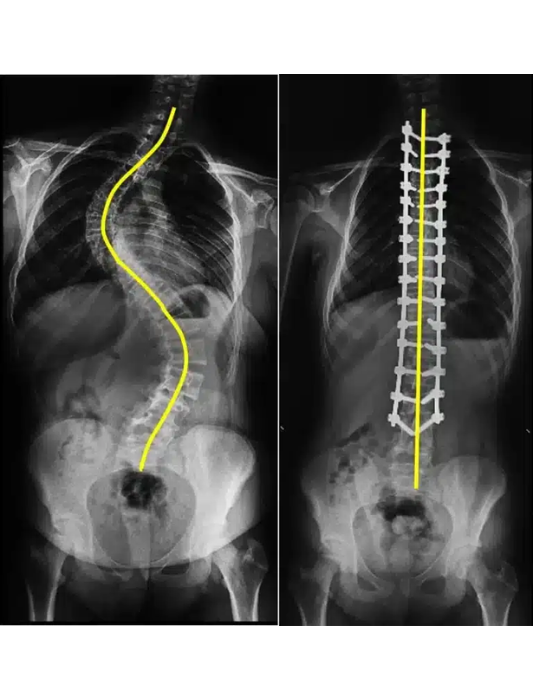

Scoliosis Surgery

Costs start from USD 12,000 to USD 20,000

Success Rate 80–90%